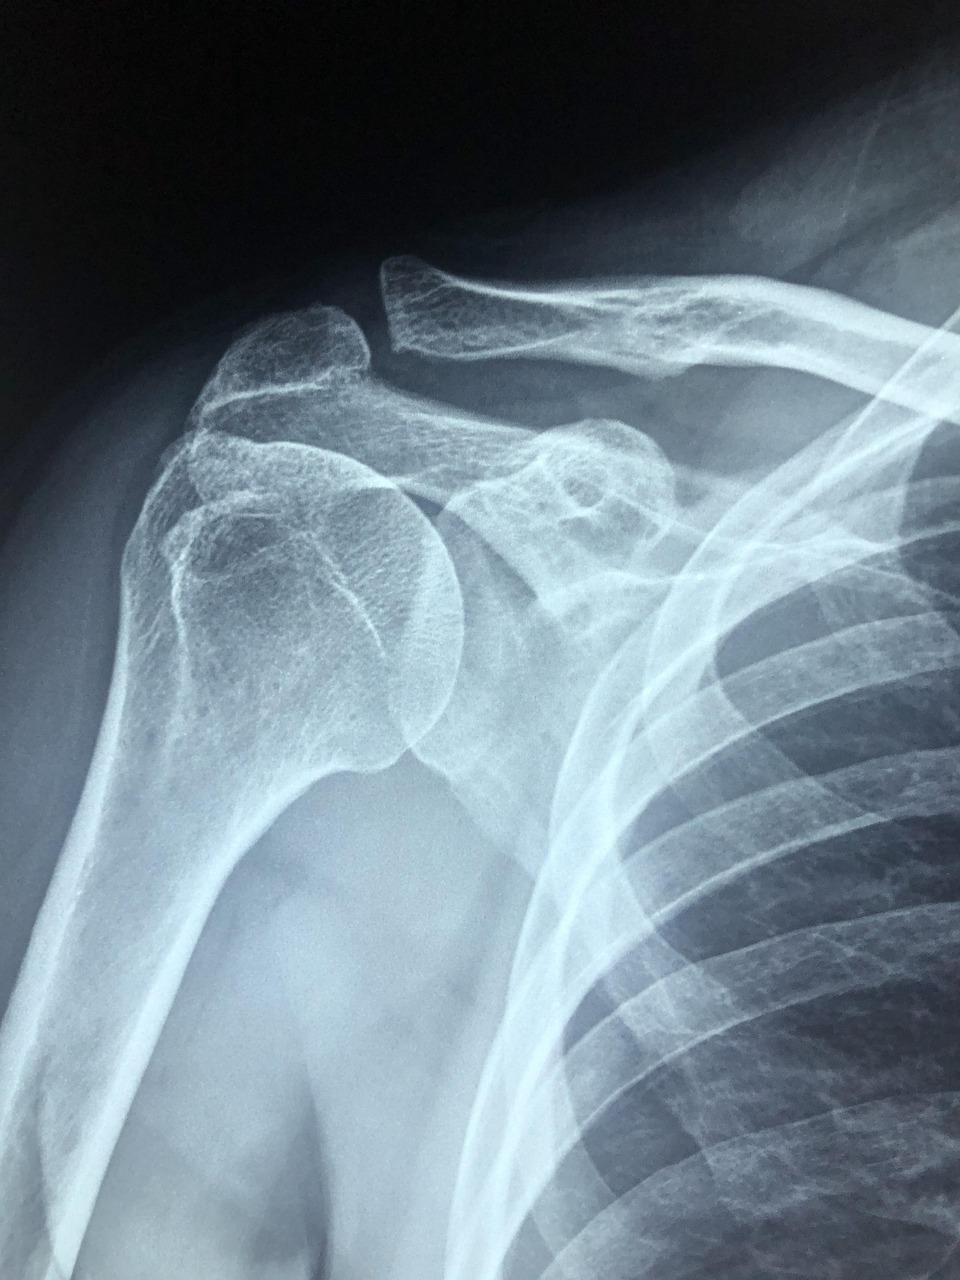

- 정기적으로 골밀도 검사 받기 🩻